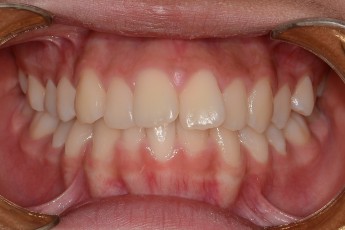

- 덧니교정

Before

After